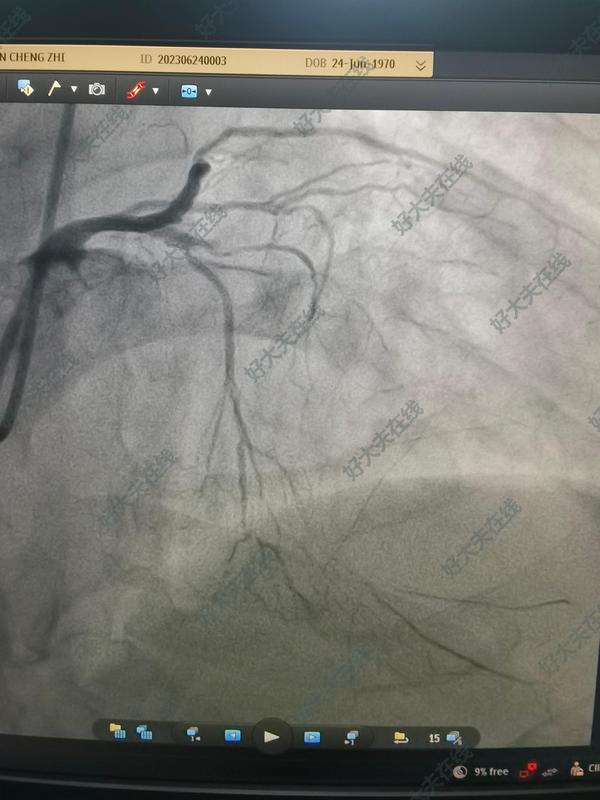

治療前 冠心病 嚴(yán)重三支病變 不適合搭橋 支架需要五個以上 而且效果均不佳 ?;颊咭才懦庖陨现委煟詈笫褂盟幬锴蚰议_通所有血管。前三張是治療前,后三張是治療后,介入治療時間兩個半小時。 治療中 開通閉塞病變,藥物球囊處理 治療后 治療后即刻 無不適